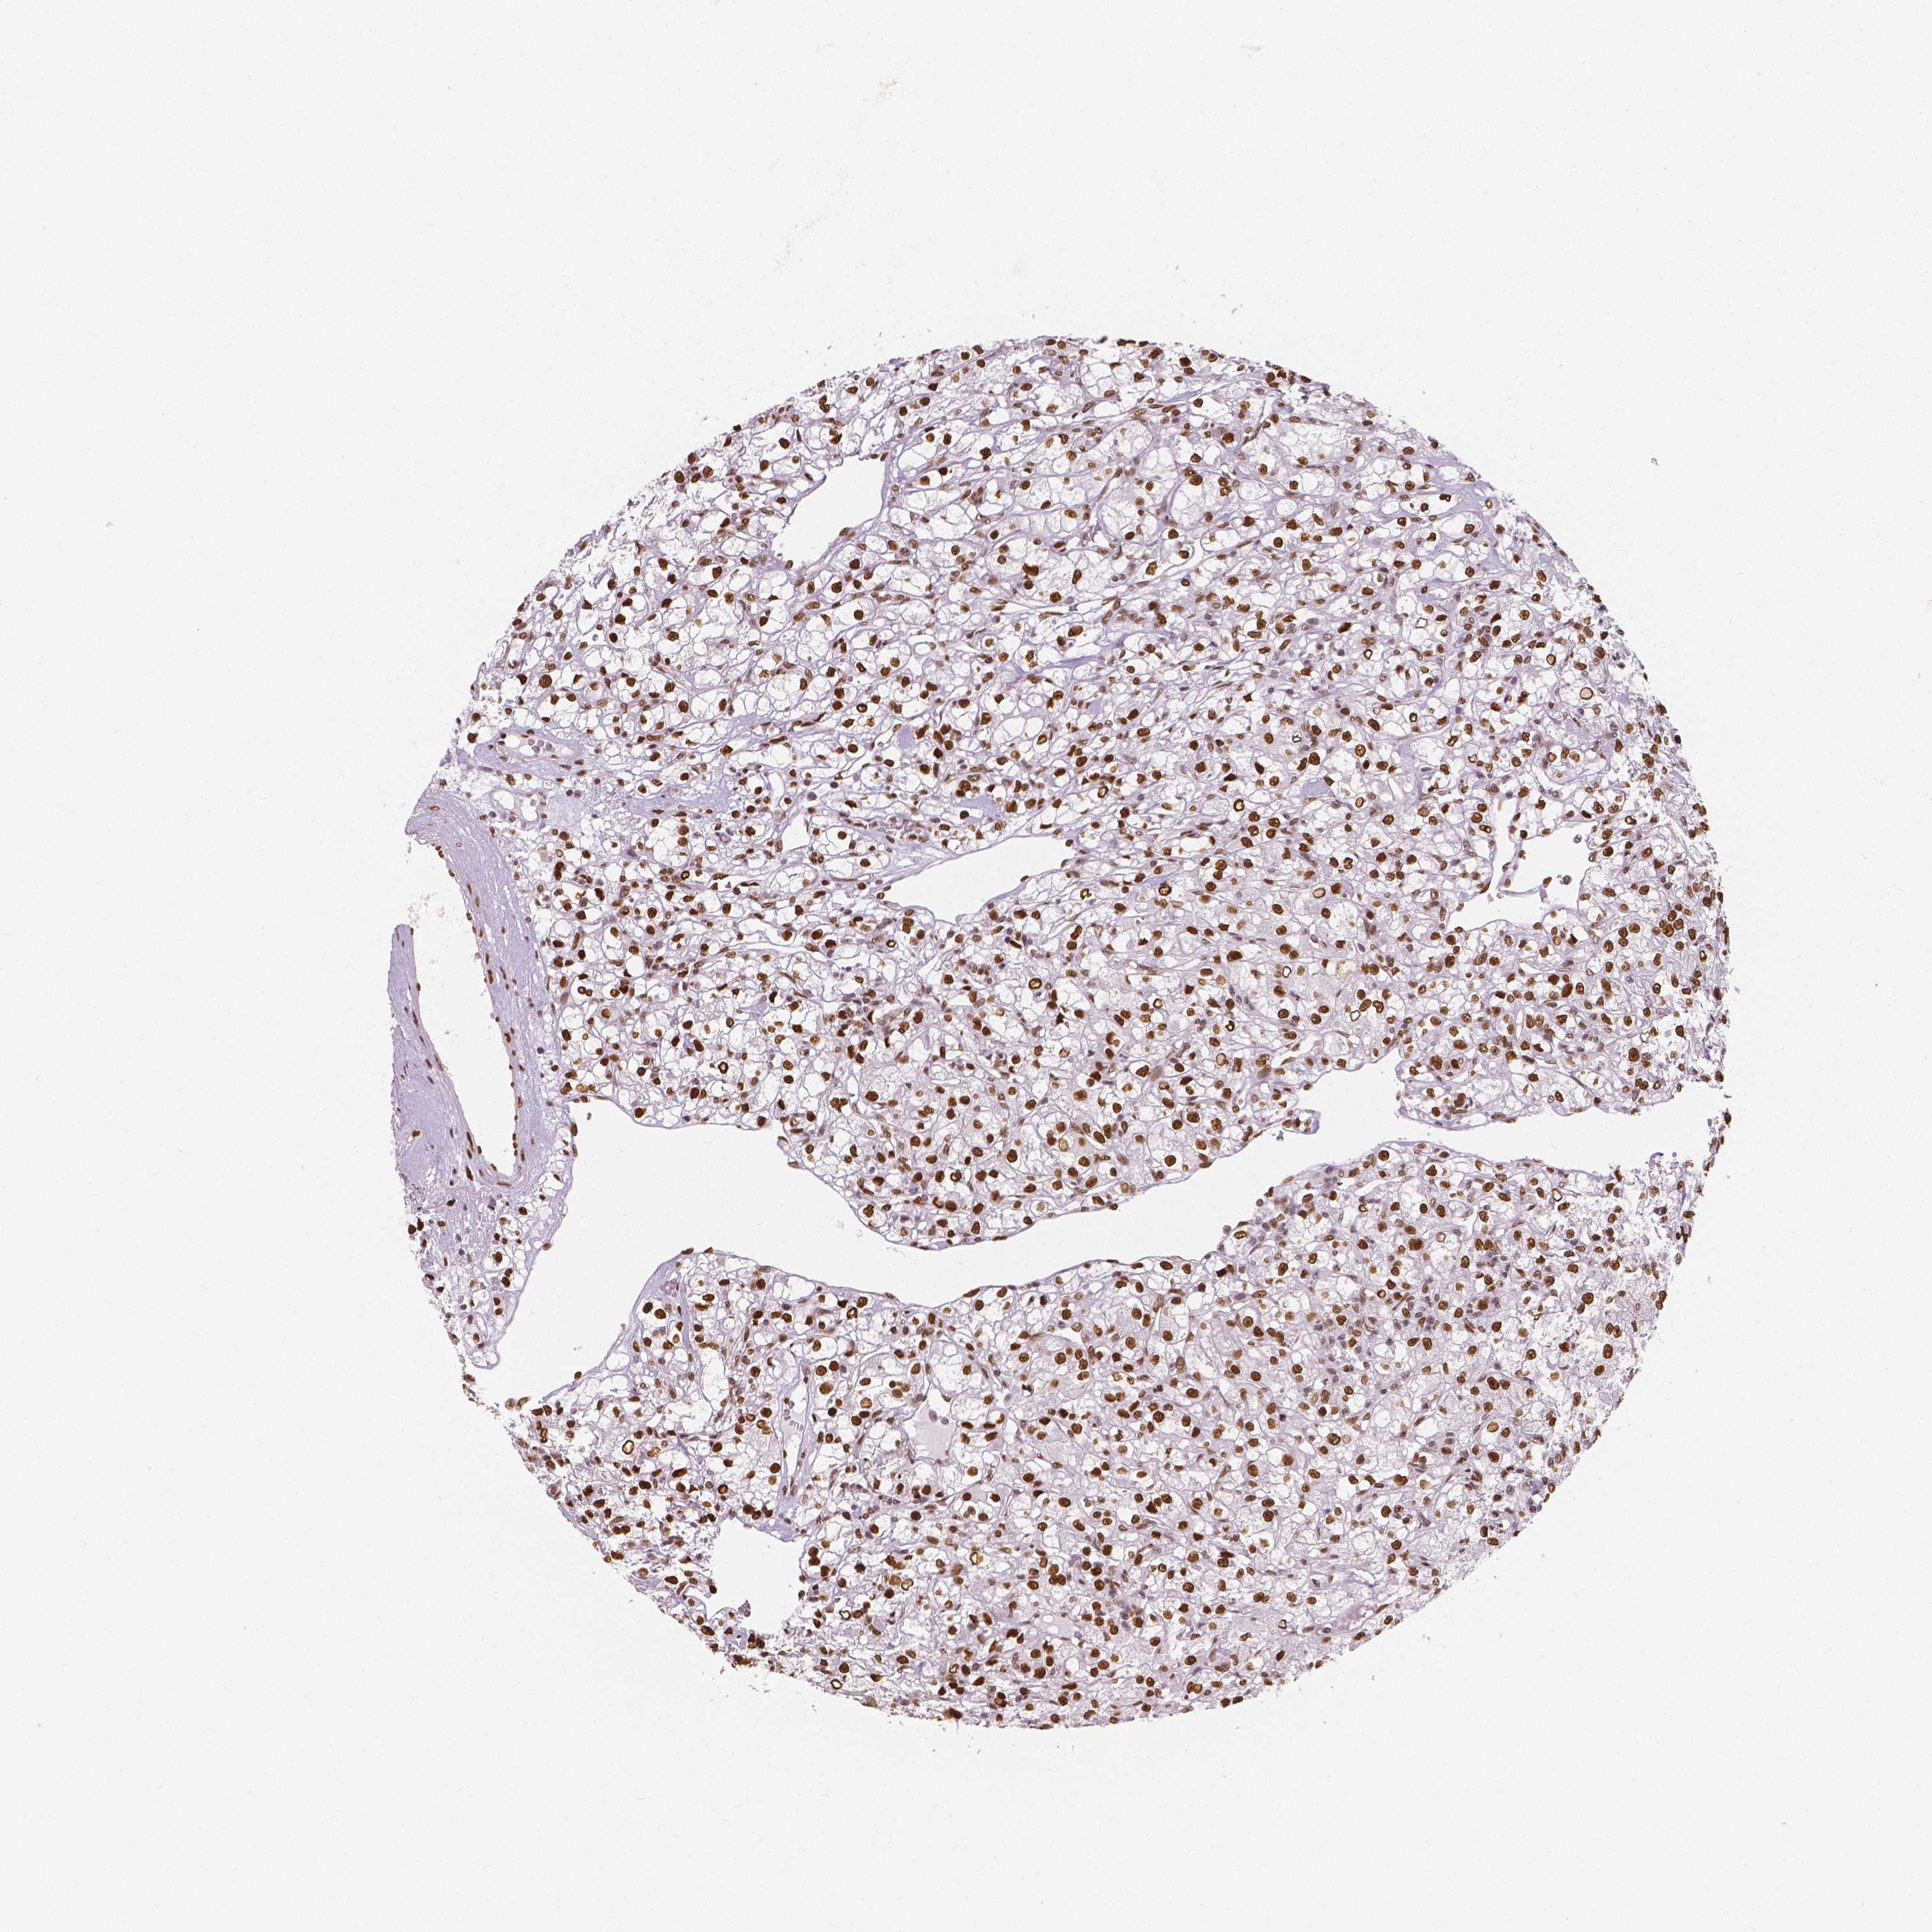

CANCER RENAL CANCER Show tissue menu

Renal cancer

Kidney chromophobe

Kidney renal clear cell carcinoma

Kidney renal papillary cell carcinoma